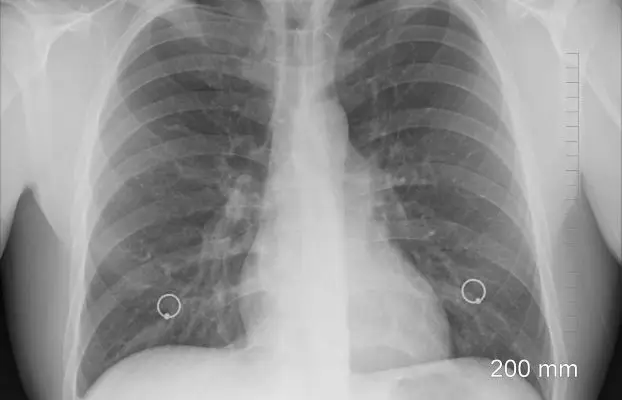

Erken evredeki bir akciğer kanserini teşhis etmenin en güvenilir yolu Dünya Sağlık Teşkilatının da önerdiği şekilde ‘akciğer kanseri gelişmesi açısından yüksek riskli olan kişilerin’ düzenli olarak her yıl bir kez düşük doz, tarama amaçlı bilgisayarlı tomografi çektirmesidir.